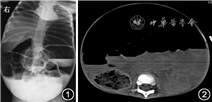

患儿 女,1岁11月龄,因“腹胀、呕吐20 d,加重2 d”于2020年7月收入山东第一医科大学附属省立医院小儿重症医学科。入院前20 d患儿出现腹胀,伴呕吐,2~3次/d,呕吐物为少量胃内容物,非喷射性,未予特殊处理;入院前15 d呕吐好转,仍有腹胀,后于外院治疗,腹胀无缓解;入院前2 d腹胀较前加重,遂至山东第一医科大学附属省立医院门诊,立位腹X线片示肠管明显扩张并积气,可见多个阶梯状气液平面(图1),查血常规及肝功生化示血小板降低(84×109/L)、钾降低(1.84 mmol/L),拟诊“肠梗阻、低血钾、血小板减少症”收住院。患儿发病以来,精神尚可,进食量较前减少,尿量可,排便1~2次/d,为少量黄色稀便。患儿系其母第2胎第2产,足月经剖宫产出生,出生体重4.2 kg,母亲孕期体健,否认生后窒息缺氧史,生后体重增长缓慢。父、母及兄均体健。家族史无特殊。

影像学检查:腹部CT示腹盆部明显膨隆,胃腔及部分肠管明显扩张并积气,可见多个阶梯状气液平面,腹腔肠管拥挤,结构显示不清。肝脏大小、形态可,胆囊、胰腺显示不清。脾脏及双肾平扫未见明显异常密度灶。膀胱空虚,内见导尿管影。子宫显示不清。腹盆腔未见明显增大淋巴结及明显积液影(图2)。